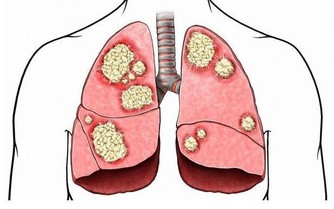

1、心源性疾病:如慢性心臟功能不全、心衰等;

2、腎臟疾病:如腎功能不全、腎病綜合症等;

3、血管疾病:如靜脈瓣功能不全、靜脈迴流障礙、深靜脈血栓等;

4、肝臟疾病:如慢性肝臟疾病,血液中的白蛋白數量下降、血液滲透壓下降,也會引起腳腫。